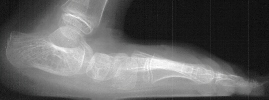

A six year old female followed for spastic quadriplegic cerebral palsy presented with increasing difficulty with ambulation secondary to bilateral hamstring tightness and progressive planovalgus deformity of the feet. Examination revealed a small thin six year-old female with severe bilateral planovalgus deformity which has become a progressive problem. While walking, the bilateral planovalgus deformity causes her to bear weight on her medial midfoot.

On weight bearing x-rays the talocalcaneal angle is 44 degrees and talonavicular angle is 40 degrees. This indicates that surgery is definitely indicated.